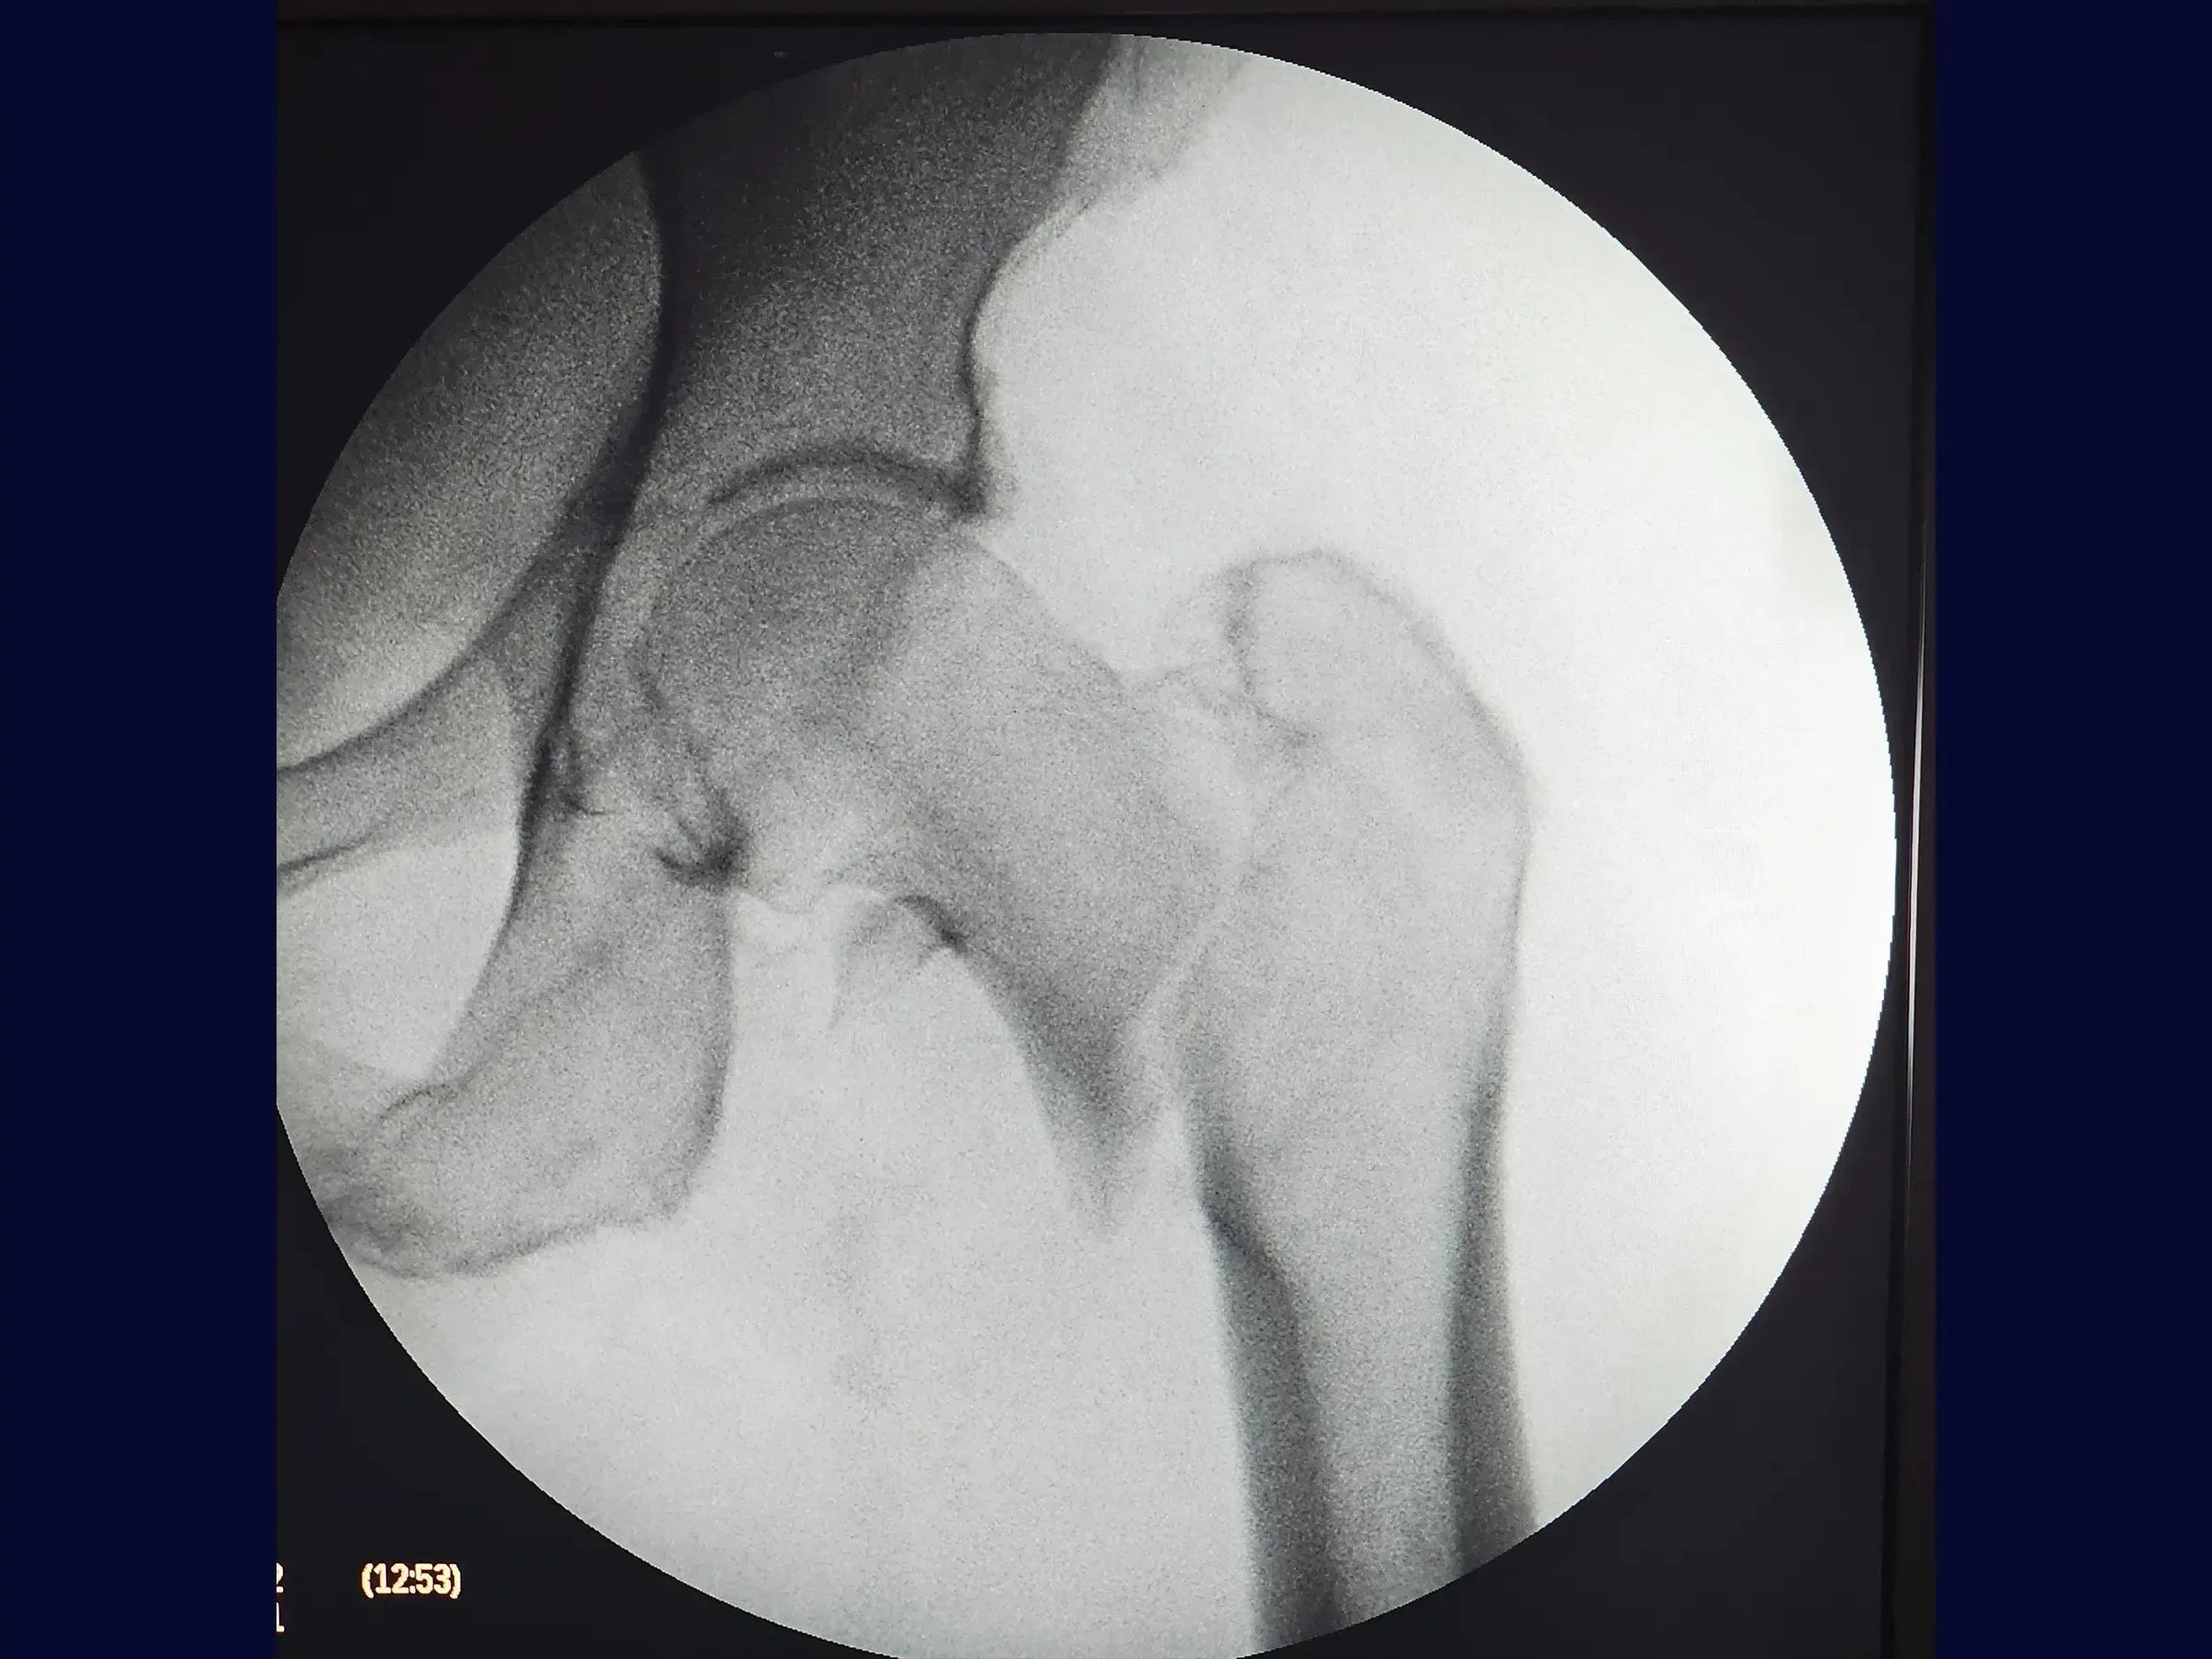

El tratamiento de fracturas inestables de fémur proximal en pacientes de edad avanzada plantea un desafío técnico significativo, que a menudo dificulta la correcta ejecución quirúrgica. Esta capacitación ofrece una inmersión práctica en la osteosíntesis de fémur proximal con enclavado intramedular, presentando un enfoque optimizado que incluye el posicionamiento sin mesa de tracción y la maniobra de "balancín", todo ello detallado en video de alta resolución desde una perspectiva quirúrgica para facilitar su replicación.

- Osteosíntesis de fracturas inestables del fémur proximal con clavo intramedular.

- Maniobra de reducción en balancín para fracturas impactadas y en valgo.

- Clavo Intramedular Corto: Abordaje sistemático para la inserción del clavo y la extracción de la guía, considerando los desafíos de la impactación y el desplazamiento en valgo.

- Maniobra de reducción en balancín: Demostración de la técnica de reducción para fragmentos proximales valgos o impactados, incluida la creación de un miniportal seguro y la aplicación de la palanca para obtener y mantener la reducción anatómica con una manipulación mínima.